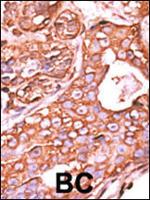

PPM1F Polyclonal Antibody

WB IHC (P)

货号 PA5-15571

WB IHC (P) ICC/IF ELISA

货号 PA5-112664